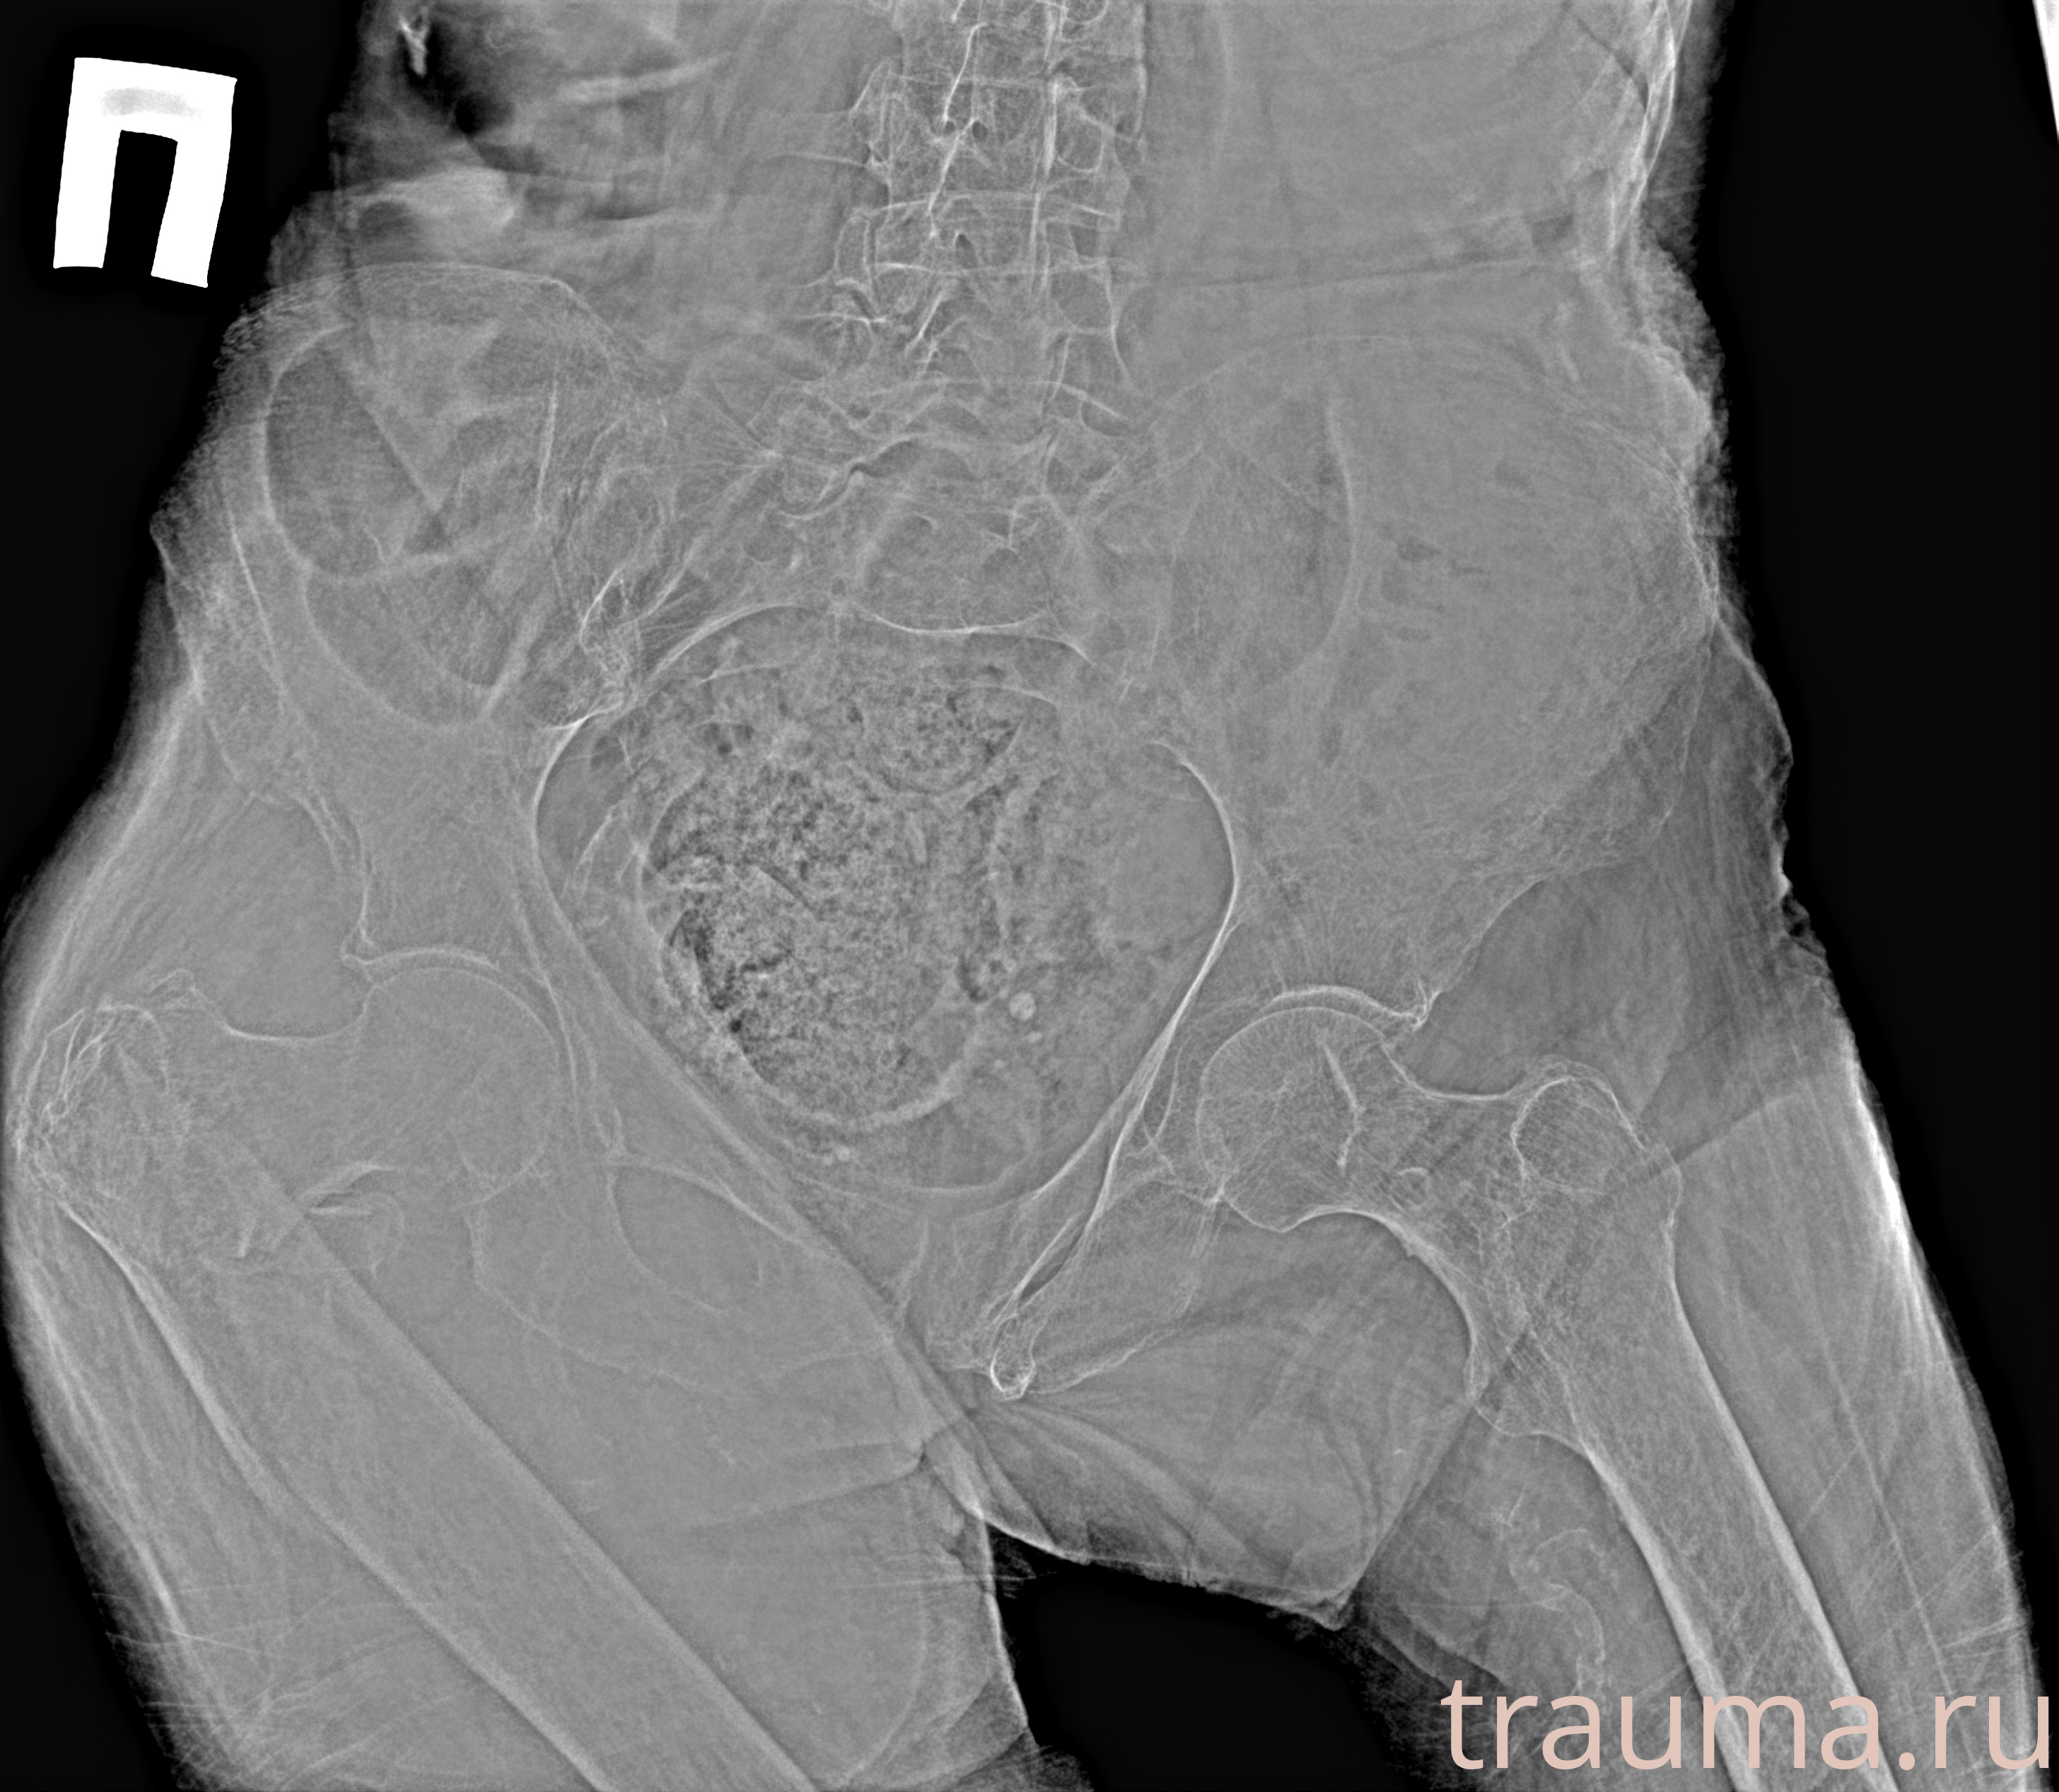

Рентгенограммы

Рентген на дому: по вашему адресу приезжает врач-рентгенолог, травматолог-ортопед с мобильным рентгеновским аппаратом, проводит диагностику травмы или заболевания, делает необходимые рентгенограммы, дает рекомендации по дальнейшему лечению. Получить качественные снимки в домашних условиях возможно благодаря уникальной методике, разработанной МосРентген Центром для института  Склифосовского